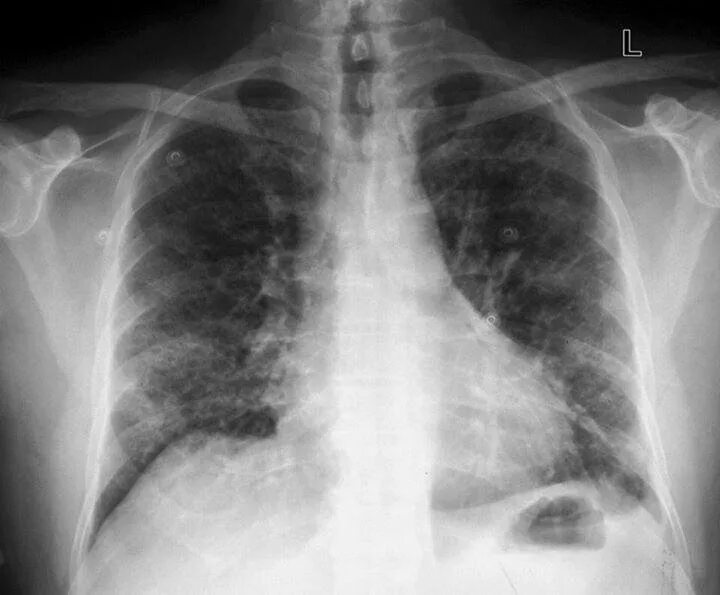

1 инфильтрат